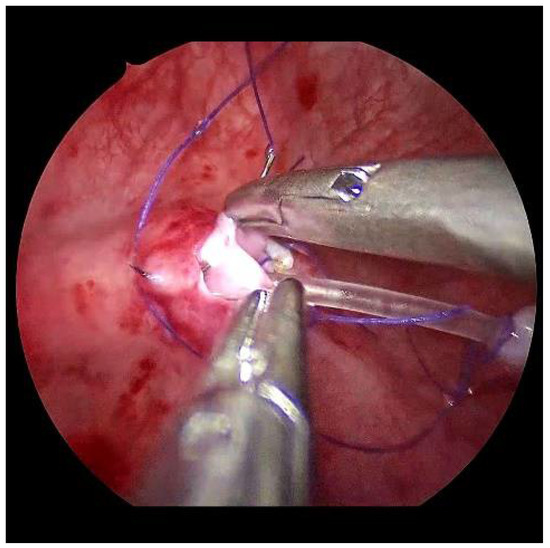

Submucosal tunnel preparation using curved scissors often requires some patience. When the tunnel is finished, the refluxive ureters are now shifted to the opposite side equivalent to the open approach. An ipsilateral suture fixes the ureter to the detrusor (Figure 6).

Figure 6. To reduce the tension on the neoostium, the ureter is pexed at the bladder entrance.